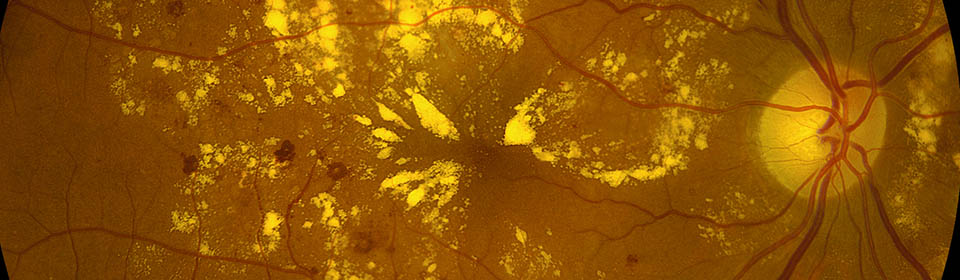

Almost 1 in 10 diabetics has sight threatening retinopathy.

Diabetes is the leading cause of blindness in the 25 to 75 age group.